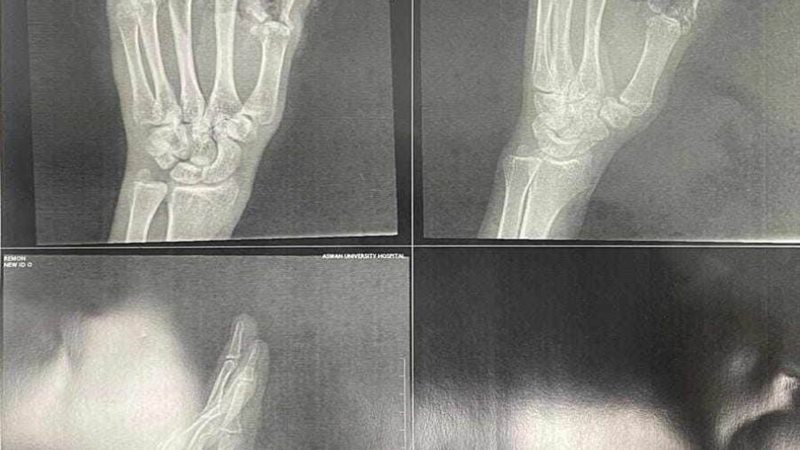

نجح فريق من الجراحين بقسم التجميل بمستشفي جامعة أسوان، في إجراء جراحة دقيقة نادرة لشاب أصيب ببتر في ثلاثة أصابع فى يده اليسرى، من جراء استعماله لساطور نتج عنه قطع الدموية والأوتار والأعصاب والعظام بأصابع اليد، تم إعادة تركيب الأصابع، وإعادة الدورة الدموية لكف اليد مرة أخرى، عقب التدخل الجراحي السريع للتعامل مع الحالة بدقة وعناية فائقة.

وقال الدكتور محمد زكي الدهشوري، عميد كلية الطب بأسوان، خلال بيان صحفي صادر عن جامعة أسوان اليوم السبت، أن المستشفى الجامعي استقبل المريض بقسم الاستقبال والطوارئ، وتم على الفور دخوله مباشرة للعمليات والطوارئ بقسم التجميل والإصلاح، وتكليف فريق متخصص من الجراحين بإجراء الجراحة العاجلة، والعمل على إعادة أصابع اليد المبتورة قبيل موت الأنسجة ، فيما تم حجز الحالة بقسم التجميل لتلقي العلاج اللازمة واستقرار الحالة الصحية.